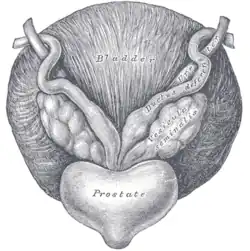

Fundus of the bladder with the vesiculae seminales.

Fundus of the bladder with the vesiculae seminales.

Structure

The human seminal vesicles are a pair of glands in males that are positioned below the urinary bladder and at the end of the vasa deferentia, where they enter the prostate. Each vesicle is a coiled and folded tube, with occasional outpouchings termed diverticula in its wall.[2] The lower part of the tube ends as a straight tube called the excretory duct, which joins with the vas deferens of that side of the body to form an ejaculatory duct. The ejaculatory ducts pass through the prostate gland before opening separately into the verumontanum of the prostatic urethra.[2] The vesicles are between 5–10 cm in size, 3–5 cm in diameter, and have a volume of around 13 mL.[3]

The vesicles lie behind the bladder at the end of the vasa deferentia. They lie in the space between the bladder and the rectum; the bladder and prostate lie in front, the tip of the ureter as it enters the bladder above, and Denonvilliers' fascia and the rectum behind.[3]